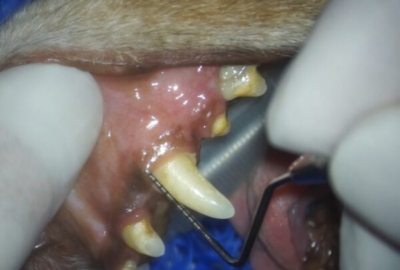

歯科レントゲンの次は、プロービングといって歯周ポケットの深さや動揺の有無、根っこの分岐が見えてしまっていないかなどのチェックをします。

右犬歯の手前に5mmの歯周ポケット

奥には10mmの深い歯周ポケット

小型犬の健康な歯周ポケットは3mmまででしょうから、かなり深いポケットです。上顎犬歯は左右とも同様の深いポケットで鼻腔とつながっており基礎疾患と年齢から、残念ながら抜歯を選択しました。口腔鼻腔ろうはこのままですと、くしゃみや鼻水、食欲不振、最悪肺炎まで起こしかねません。